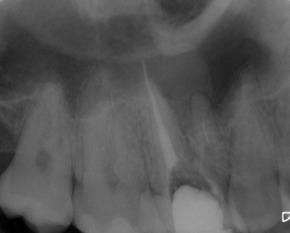

Nach erfolgter Information über die vermutete Prognose unternehmen wir den Versuch, das frakturierte Instrument darzustellen. Nach Entfernung der Aufbaufüllung werden die Kanaleingänge dargestellt (Abb. 2). Es zeigt sich, dass neben dem distovestibulären Kanal auch ein vierter Kanal (mb2) vorhanden ist. Die Darstellung der Wurzelkanaleingänge erfolgt in unserem Haus mit dem Aufsatz 1R des Tigon+. Dank der Abwinkelung des Instruments profitiert man von einer sehr guten Sicht auf die Behandlungsstelle. Zudem erlaubt es ein schnelles und gezieltes Abtragen von Dentin, ohne dabei den Zahn unnötig zu schwächen.

Nach Darstellung aller Wurzelkanaleingänge wird in einem zweiten Schritt das frakturierte Wurzelkanalinstrument dargestellt (Abb. 3 u. 4). Hierfür verwenden wir den Aufsatz 3E des Tigon+. Durch die schmale und lange Form des Instruments erreichen wir einen tiefen und schmalen Zugang.